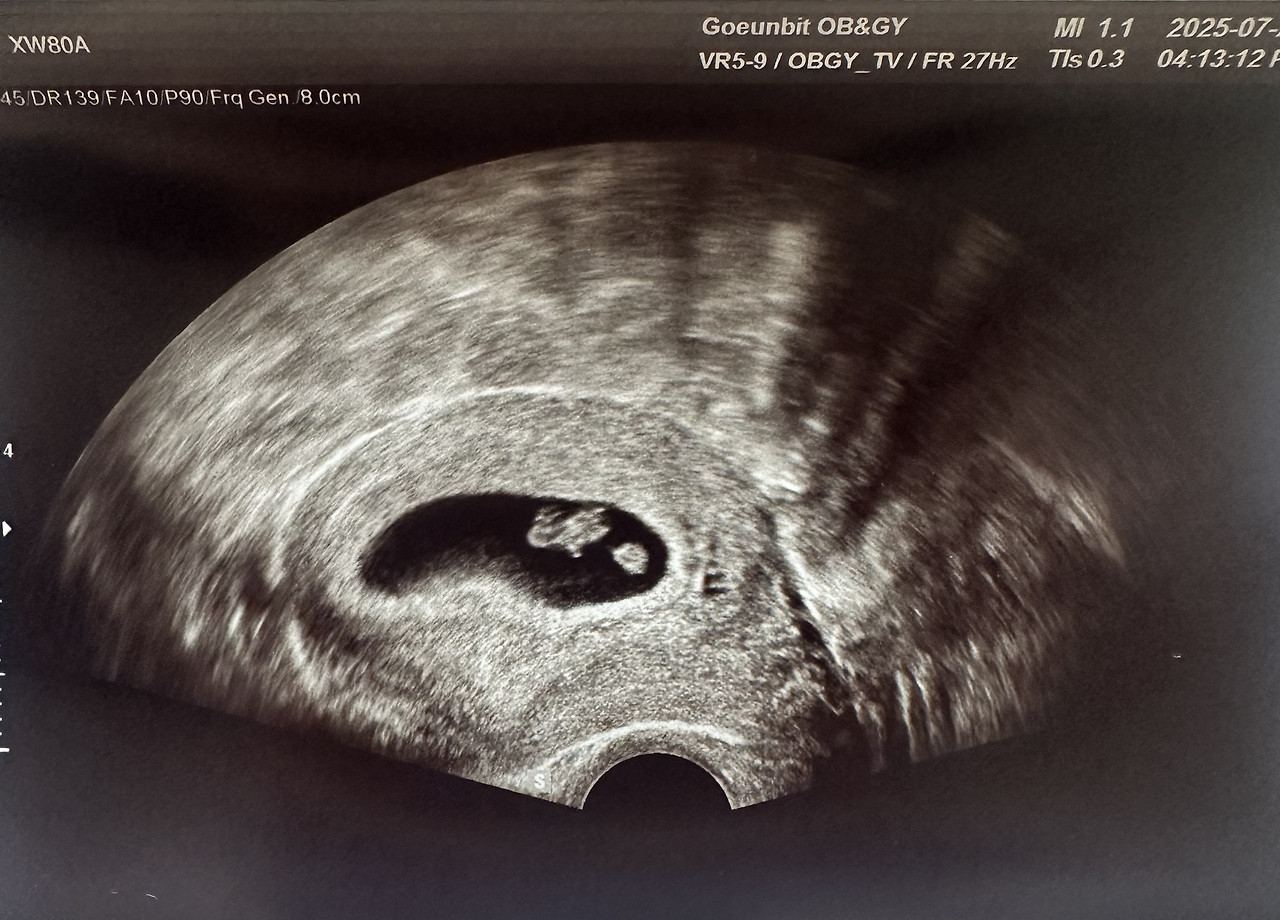

7주 차, 심장 소리를 듣다

드디어 아기의 심장 소리를 들었다.

7주 차 아기의 모습. 작지만 또렷하게 심장이 뛰고 있었다.